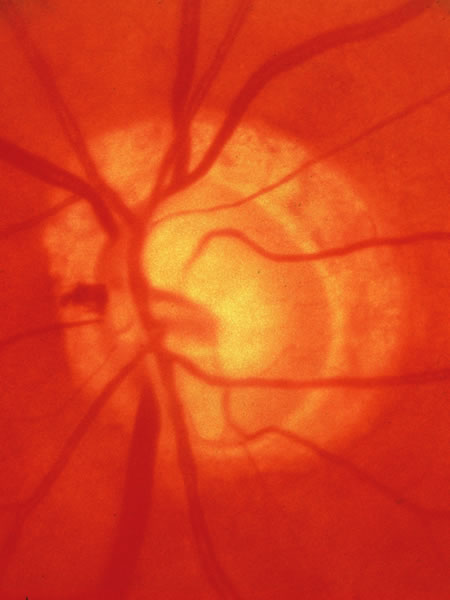

The approximately 1 to 1.5 million axons that form the optic nerve arise from the retinal ganglion cells and course toward the optic disc in a well-known pattern (Fig. 1). From the nasal retina the fibers take a straight course toward the disc. Axons originating temporal to the fovea arc around the macula to enter the upper and lower poles of the optic nerve head. The macula fibers pass directly to the temporal quadrant of the disc in the papillomacular bundle.

Fig. 1. Fundus photograph shows the normal pattern of the retinal nerve fiber layer. (Courtesy of P. Juhani Airaksinen, MD).